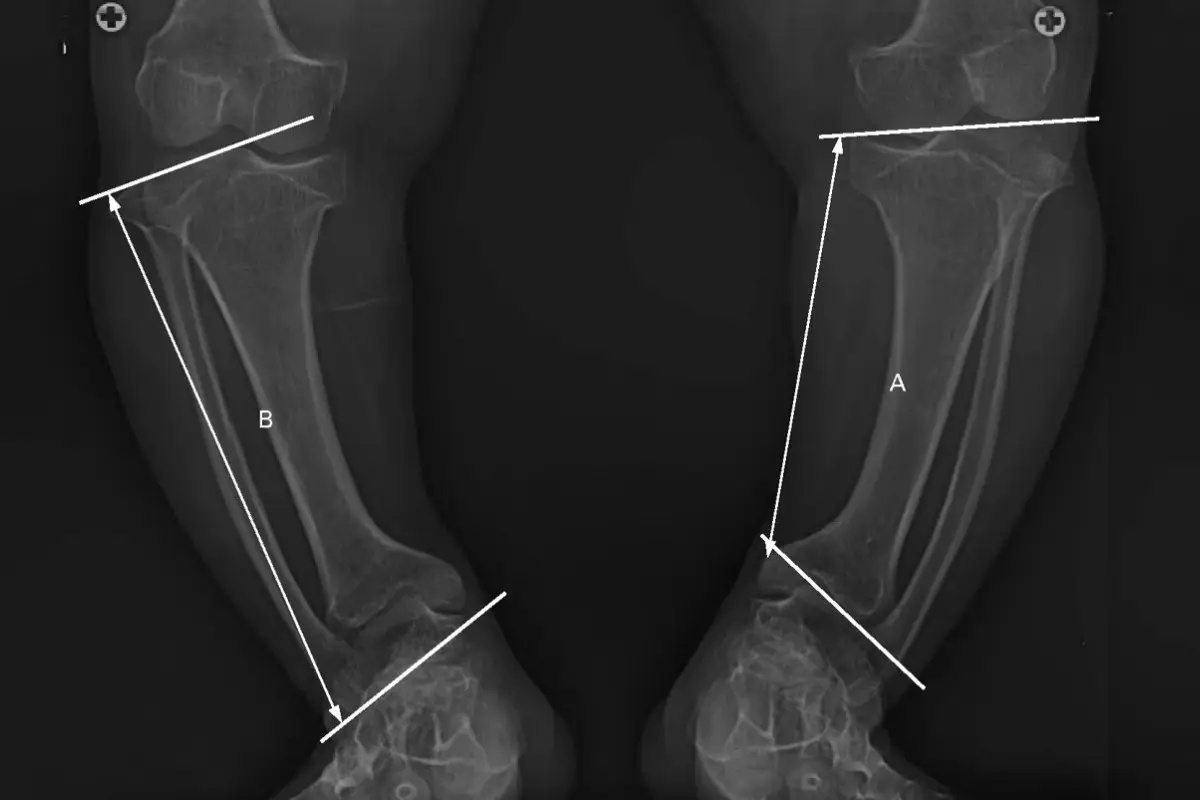

پای پرانتزی وضعیتی است که در آن استخوانهای پا نسبت به هم زاویه پیدا میکنند، به طوری که وقتی مچ پاها به هم نزدیک هستند، زانوها از هم فاصله دارند. این وضعیت باعث میشود که پاها حالت قوسدار و شبیه حرف O پیدا کنند.

استخوانها نرم و شکننده هستند و تحمل وزن بدن را ندارند. درمان شامل مکملهای ویتامین D و اصلاح رژیم غذایی است. - پای پرانتزی ناشی از بیماری بلانت (Blount Disease):

این بیماری یک اختلال رشد در استخوان درشتنی است و باعث افزایش زاویه پرانتزی میشود. برخلاف نوع طبیعی، خودبهخود اصلاح نمیشود و نیازمند درمان است. - پای پرانتزی ناشی از ناهنجاریهای مادرزادی یا ژنتیکی: